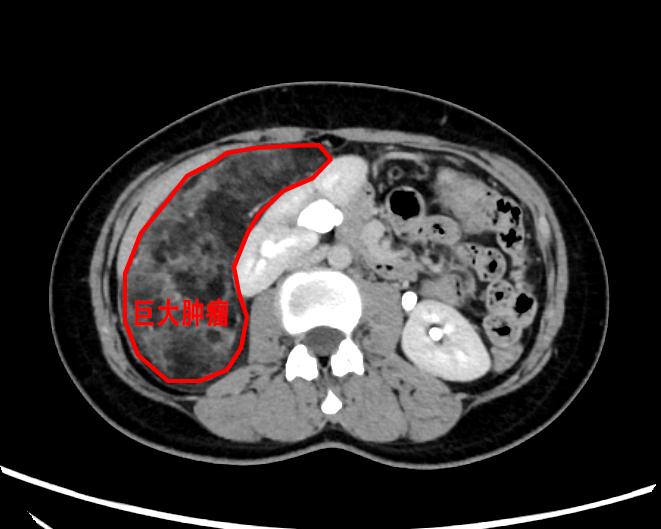

入院后,经增强CT提示右侧腹膜后巨大富脂肪肿瘤,肿瘤上界达右侧膈下,下界至盆腔,几乎占据整个右侧腹膜后间隙,考虑为血管平滑肌脂肪瘤。尽管该肿瘤为良性肿瘤,但体积如此之大并不常见,如行开腹手术则手术切口可长达30cm以上,对患者创伤大,且术后恢复慢、疼痛明显。鉴于患者为年轻女性,经充分考虑后,我院季惠翔教授、支轶教授决定行经腹腹腔镜腹膜后肿瘤切除术,并制定了周密的手术方案。